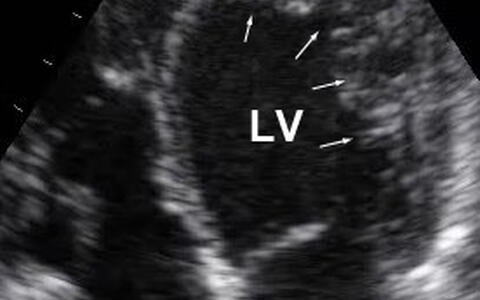

In a patient with LVNC, sponge-like muscle tissue protrudes into the left ventricle (above right as indicated by arrows) and impairs the heart’s ability to pump blood. (Picture: Sabine Klaassen/​Copyright: MDC)